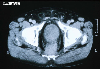

CT